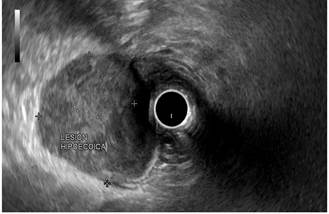

In view of the retroperitoneal mass or adenomegaly finding, which is not a usual presentation of a GIST-type tumor, an endoscopic ultrasound8 was performed using the Pentax-Noblux, in which a subepithelial lesion located in the greater curvature of the junction of the antrum and the body of the stomach was identified in the endoscopic view, and a 40 x 38 mm hyperechoic lesion with well-defined borders, without calcifications or necrosis, and affecting the entire wall of the stomach was observed in the ultrasound view (Figure 3).